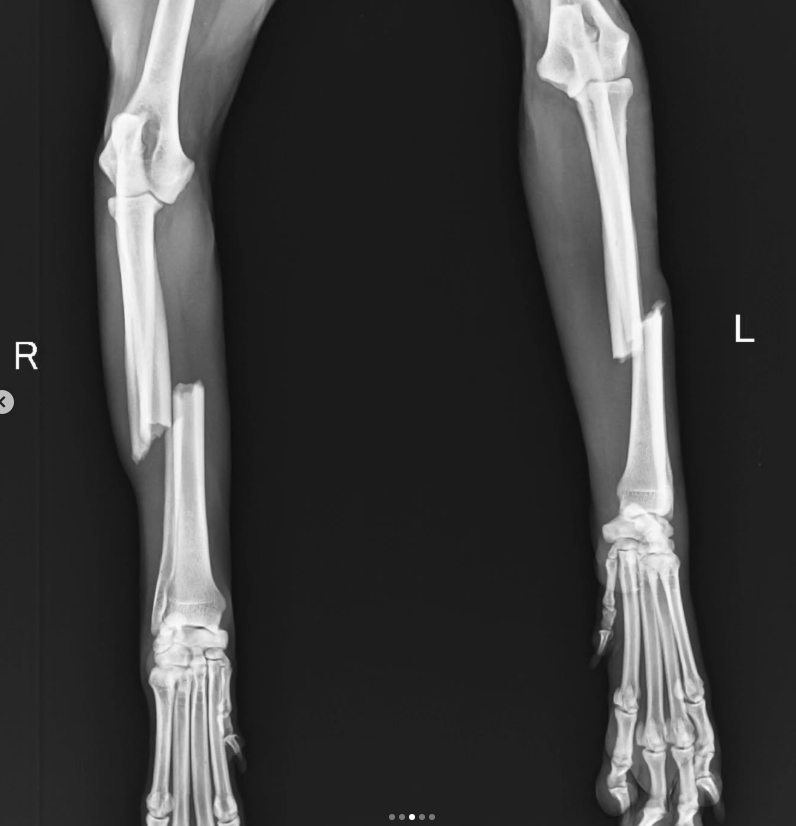

Nova is going to go in for surgery today. The breaks in his leg need plating and implants…they won’t fix with just splints.

If you look at slide 3 you can see how bad the breaks are. I can’t even imagine the pain he is in. ๐ And yet he’s so cooperative and wags his tail..